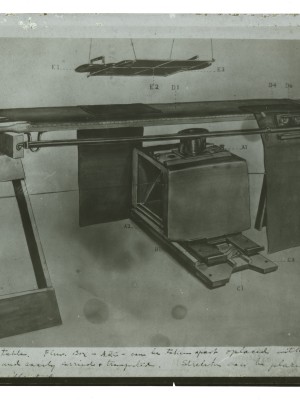

Dr. Edwin Ernst, an only child born to St. Louis residents Charles and Catherine Ernst, was a notable Roentgenologist, a physician who specializes in radiological work. Dr. Ernst studied at Washington University in St. Louis and later at Moravian College in Bethlehem, Pennsylvania earning his advanced degrees. For two years he served as a resident physician at the St. Louis Mullanphy Hospital before leaving to pursue a private practice. When the United States formally entered the war in 1917, Ernst left St. Louis to become chief radiologist at Base Hospital 21. He was discharged honorably in 1919 with the citation of Major. His collection consist of x-ray images taken at Base Hospital 21 as well as drawings of radiological equipment and photographs.